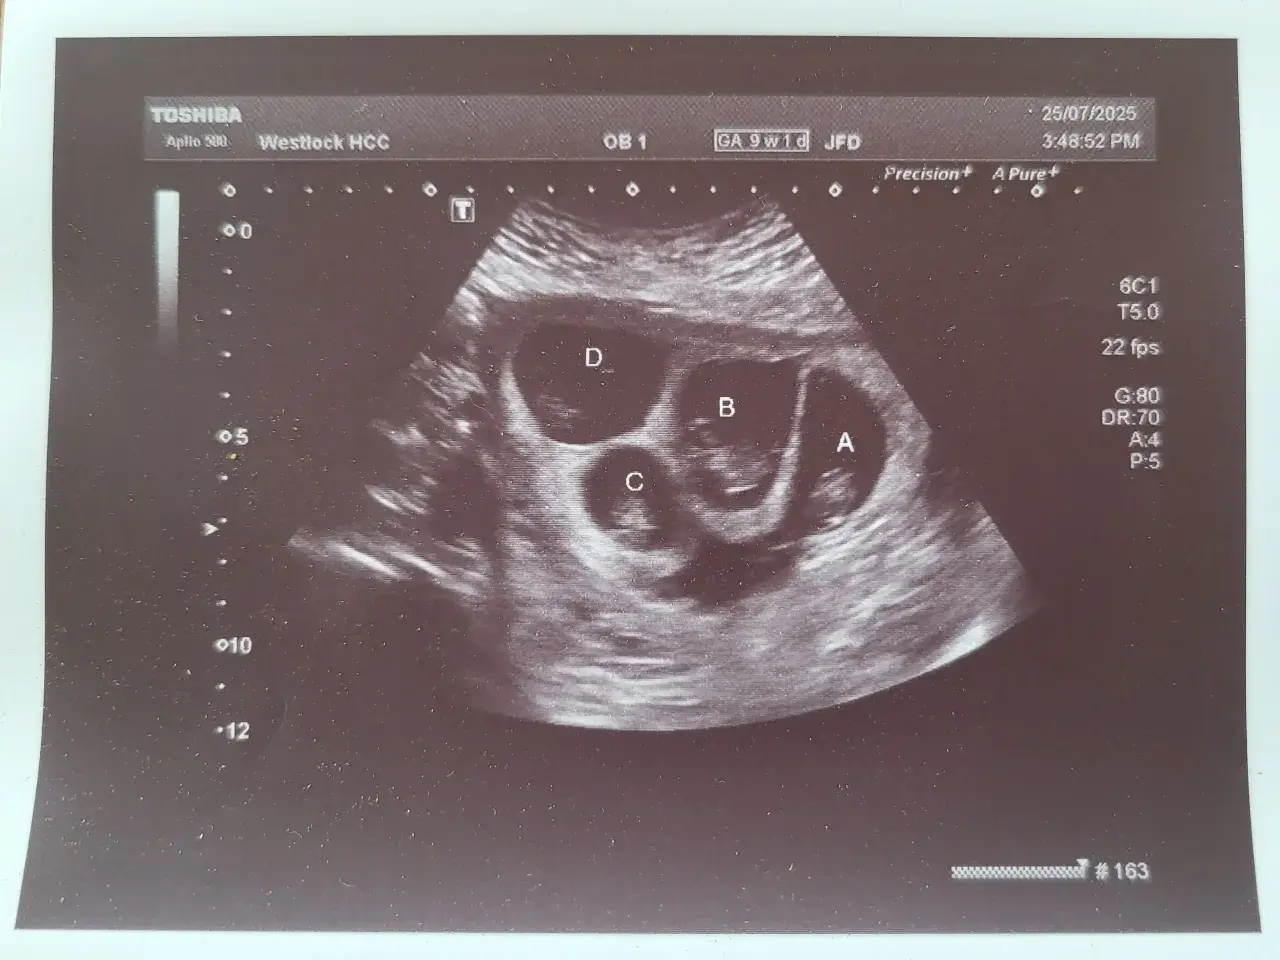

แม่ชาวแอลเบอร์ตา เตรียมต้อนรับลูกแฝดสี่

ตอนนี้เธอตั้งครรภ์ได้ 6 เดือนแล้ว และ กำลังจะมีลูกเพิ่มมาทีเดียว 4 คน โดยเป็นผู้ชาย 3 คน และ เป็นผู้หญิง 1 คน ซึ่ง "ดาร์ลีน เฮนช์" กล่าวว่า "ตอนแรกที่ฉันรู้ ฉันถึงกับช็อกไปเลย เพราะฉันไม่รู้จะรับมือยังไงดี ฉันถูกความรู้สึกถาโถมเข้ามาเต็มไปหมด ถึงขั้นควบคุมตัวเองไม่อยู่เลยล่ะ!!"

"ดาร์ลีน เฮนช์" มาจากเขตเวสต์ล็อก รัฐแอลเบอร์ตา ประเทศแคนาดา เธอเดินทางไปเอดมันตันเดือนละ 2 ครั้ง เพื่อตรวจที่คลินิกการตั้งครรภ์ความเสี่ยงสูง โดยเธอจะคลอดที่โรงพยาบาลรอยัลอเล็กซานดรา เมื่ออายุครรภ์ประมาณ 32 ถึง 34 สัปดาห์ ด้วยการผ่าตัดคลอด โดยมีทีมผู้เชี่ยวชาญ ด้านความเสี่ยงสูงพร้อมดูแล

ก่อนที่ "ดาร์ลีน เฮนช์" จะมีลูกคนแรก พ่อแม่ของเธอพยายามจะให้เธอตั้งครรภ์ มานานถึง 8 ปีเต็ม เธอต้องผ่านการรักษาภาวะมีบุตรยากหลายรอบ โดย "ดาร์ลีน เฮนช์" กล่าวว่า "มันเป็นเส้นทางที่ยาวนานมาก" และ "ฉันถูกวินิจฉัยว่ามีภาวะมีบุตรยาก แบบไม่ทราบสาเหตุ" และ "ฉันคิดว่าฉันคงจะมีลูกได้ สักคนเดียวก็ถือว่าดีแล้ว แต่ตอนนี้ฉันกลับมีเรื่อยๆน่ะสิ!!" และ "การตั้งครรภ์ลูก 4 คนในครั้งนี้ เป็นเหมือนปาฏิหาริย์!!"